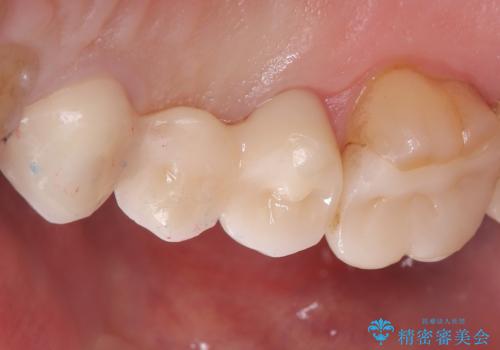

【セラミッククラウン】歯が欠けた!

右上5はう蝕除去後は間接覆髄を行いCR裏層しています。う蝕が大きく神経症状が出ないか経過を確認しクラウンの印象を行っています。